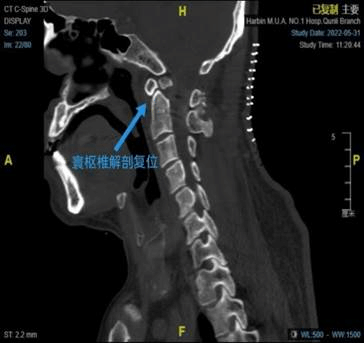

术前CT矢状位术后CT矢状位

在仔细研判张先生受伤及治疗过程,完善相关检查后赵伟教授发现,张先生在外伤后发生了寰枢椎脱位,导致脊髓受压产生四肢瘫的症状。对于确认的寰枢椎脱位,最佳的治疗方法是通过外科手术来恢复寰枢椎的正常解剖结构及稳定性。

寰枢椎部位是人体神经血管较为密集的区域,手术风险极高,手术难度极大。为了确保患者的生命安全,赵伟教授团队做了详细、充足的术前准备,并根据术前三维CT结果制定寰枢椎钉棒系统复位、植骨融合固定的手术方案